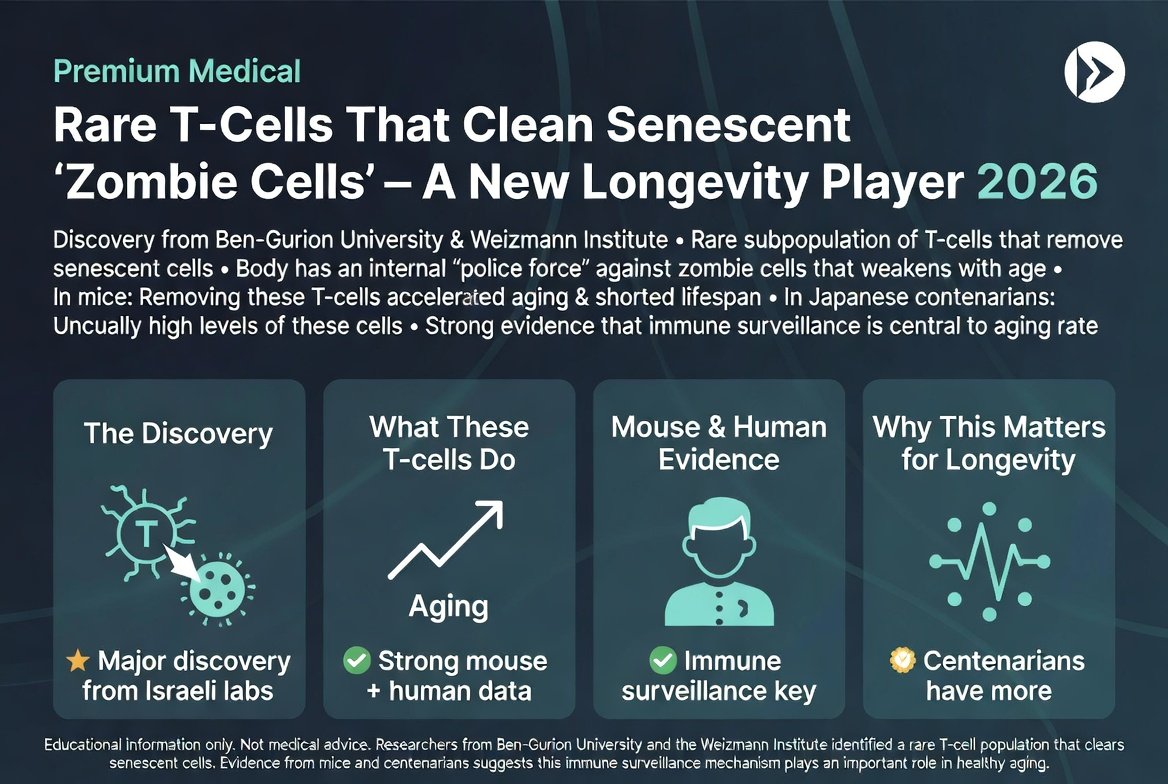

פעם בכמה זמן מתגלה משהו שמשנה את הדרך שבה אנחנו חושבים על הזדקנות, והפעם זה הגיע מהנגב. צוות חוקרים מ-אוניברסיטת בן-גוריון, בשיתוף מכון ויצמן, זיהה תת...